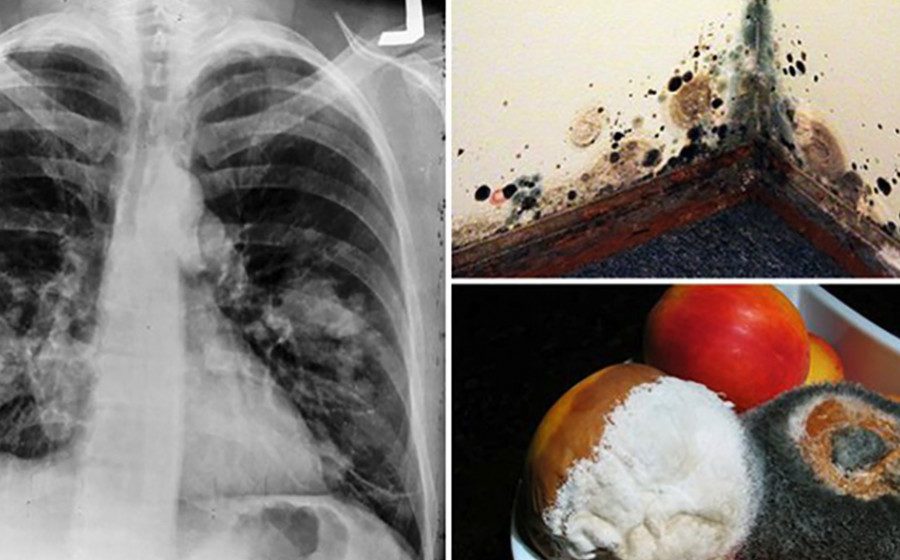

The Top 12 Cancer-Causing Products in The Average Home

It’s not easy sifting through the endless lists on the internet about products that harm the body. Immersing yourself in research can become overwhelming,...